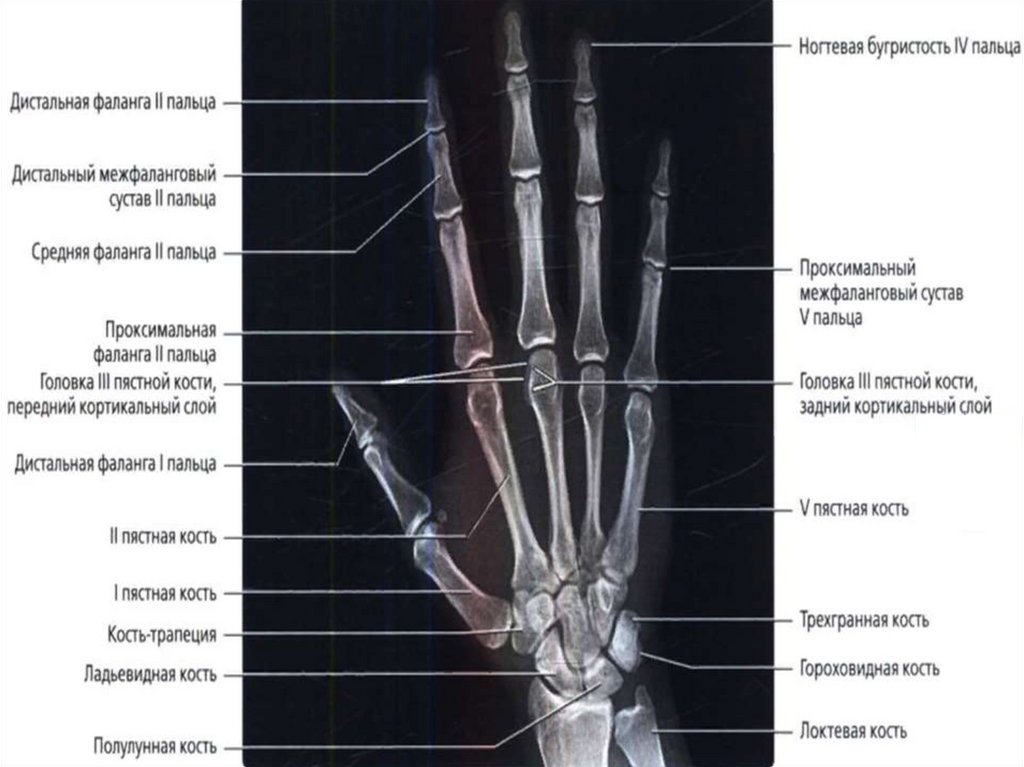

Кістки кисті – ossa manus, поділяються на зап’ясткові кістки,

п’ясткові кістки і кістки пальців, фаланги.

Зап’ясткові кістки

розміщуються в два ряди по

4 кістки в кожному і

утворюють проксимальний

і дистальний ряди.

У верхньому

(проксимальному) ряді з

латеральної в медіальну

сторону розташовані:

1) Човноподібна кістка – має

горбок човноподібної кістки;

2) Півмісяцева кістка;

3) Тригранна кістка;

4) Горохоподібна кістка.

Кістки зап’ястка – ossa carpi

1. Човноподібна кістка – os scaphoideum

2. Півмісяцева кістка – os lunatum

3. Тригранна кістка – os triquetrum

4. Горохоподібна кістка – os pisiforme

5. Кістка-трапеція – os trapezium

6. Трапецієподібна кістка – os trapezoideum

7. Головчаста кістка – os capitatum

8. Гачкувата кістка – os hamatum

П’ясткові кістки – ossa metacarpi s. metacarpalia

Cкладаються з п’яти коротких кісток, не мають назв, кожна з яких

має основу п’ясткової кістки, тіло п’ясткової кістки і головку

п’ясткової кістки.

Кістки (фаланги) пальців – phalanges digitorum

Cкладаються з основи фаланги, тіла фаланги і головки фаланги.

На головці фаланги міститься блок фаланги.

ІІ-V пальці кисті мають проксимальну фалангу, середню фалангу і

кінцеву фалангу.

Великий (перший) палець кисті - складається лише з

проксимальної фаланги і кінцевої фаланги.